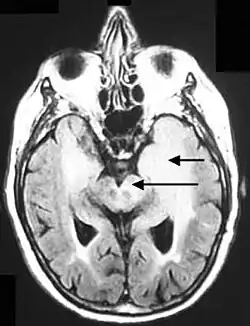

Postcontrast FLAIR of a case of meningitis. It shows enhancement of meninges at the tentorium and in the parietal region, with evidence of dilated ventricles.